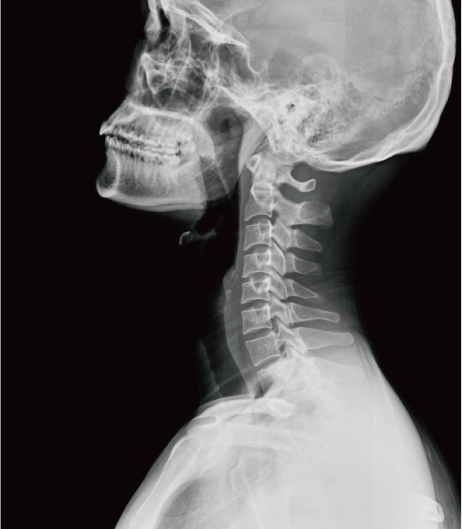

頸部片子